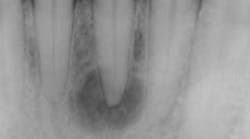

Radiographic bone changes that mimic lesions of endodontic origin can include neoplasms as well as developmental alterations. (1) The differential diagnosis behind a unilocular radiolucent lesion that can look like a typical periapical radiolucency (PAR) of endodontic origin includes: periapical cemento-osseous dysplasia (figure 1), ameloblastoma, odontogenic keratocyst, central giant cell granuloma, traumatic bone cyst, and central ossifying fibroma.